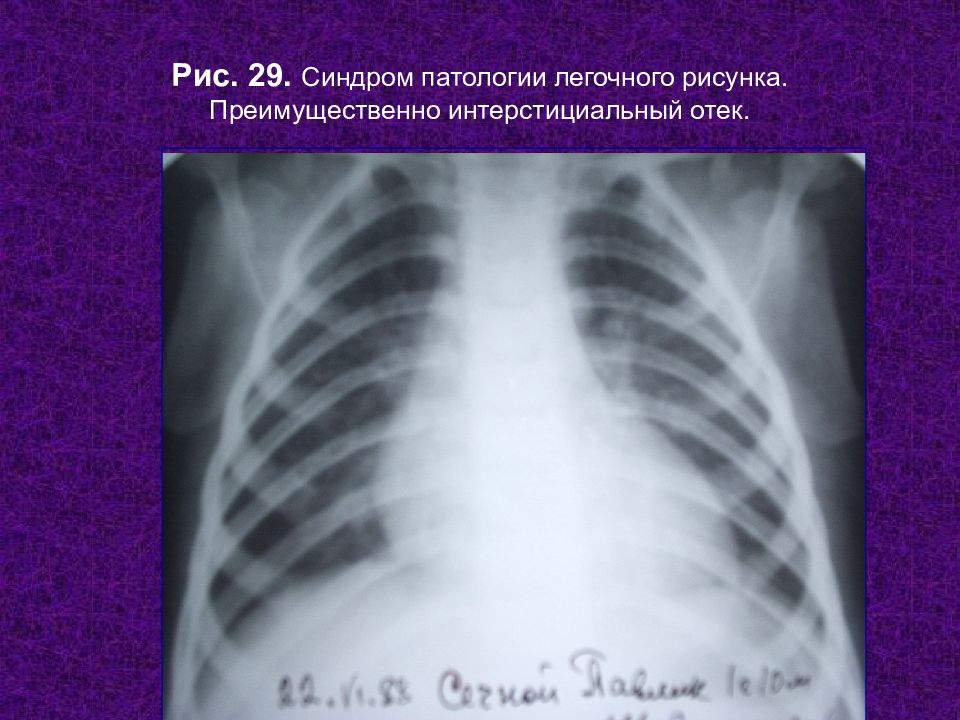

Ячеистая деформация легочного рисунка: медицинская визуализация